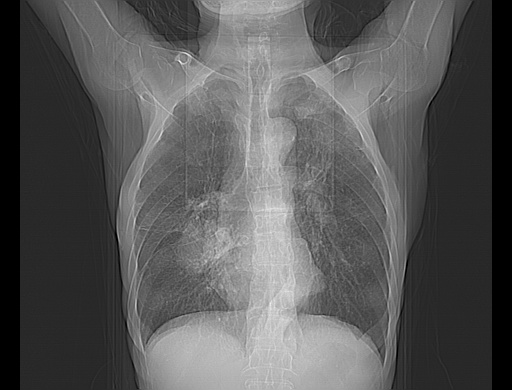

以下是引用zsl6918在2008-8-25 21:55:00的发言:[br]符合右肺周围性肺癌并肺内转移,左肺结核球。双肺肺气肿。腰椎附件转移。

以下是引用随光逐影在2008-8-25 22:03:00的发言:[br]1)考虑右肺下叶周围性肺癌并肺内转移,腰椎附件转移。2)左上肺结核(结核球形成)。3)双肺肺气肿(多发肺大泡形成)。4)双肺门区及纵隔内多发淋巴结钙化。